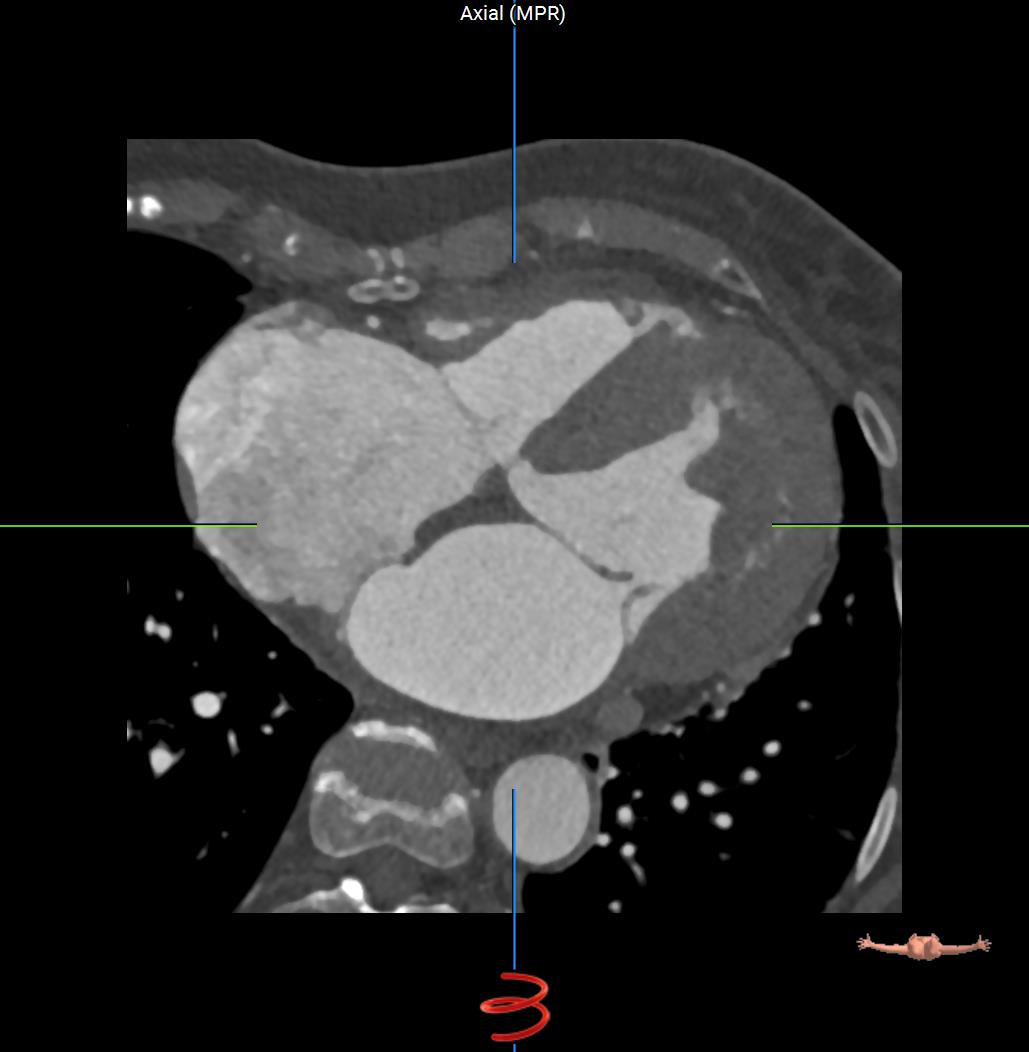

Sagittal-CT-Heart.jpgCoronal-CT-Heart.jpgAxial-CT-Heart.jpg